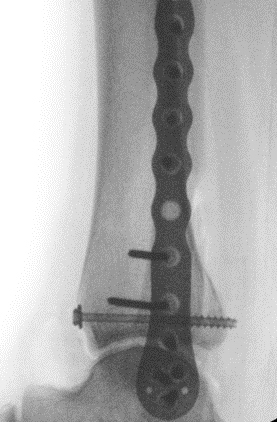

Fixation

Buttress plate

PA screws

Posterolateral buttress plate